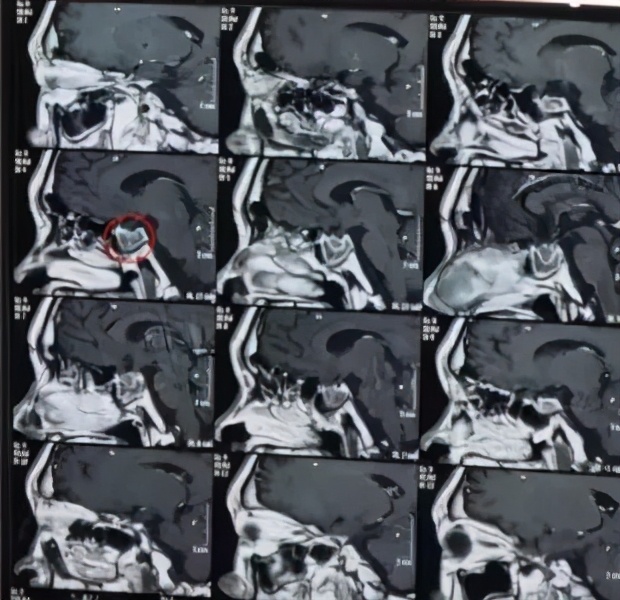

患者无外伤史,推测前肋骨折是由于上次手术心肺复苏造成。患者凝血六项检查结果提示患者现在处于高凝状态,要注意围术期血栓形成。从患者各项检查来看,患者虽经历心跳骤停、心肺复苏,但患者身体重要脏器并未受到很大影响。患者头颅核磁提示鞍区占位,考虑垂体瘤可能性。